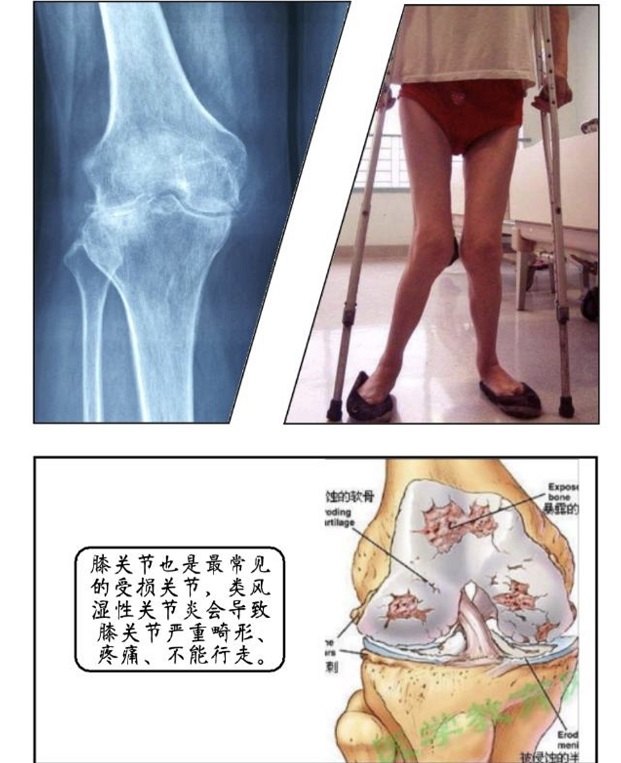

漫画说关节(三):类风湿性关节炎